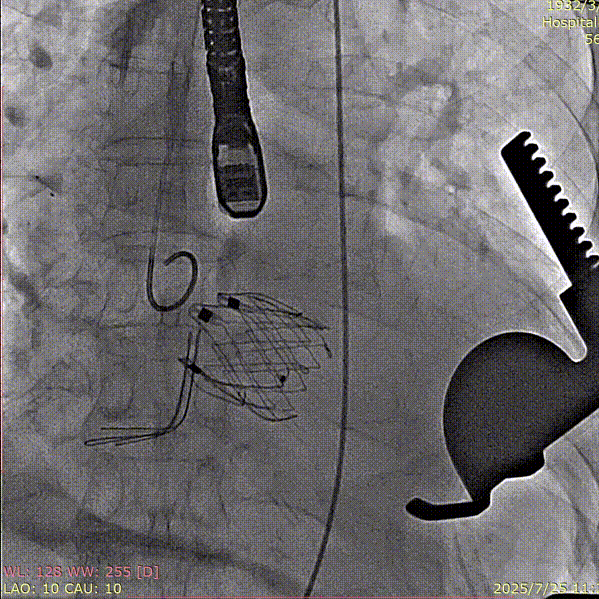

术中回顾及效果

手术过程顺利,器械操作用时仅10分钟。术中通过造影确认右冠窦居中,定位件准确入窦,瓣膜释放顺利。经超声评估,无瓣周漏,手术过程衔接流畅,未出现其他特殊情况。

术后患者恢复良好,心功能显著改善。影像复查显示瓣膜功能正常,无反流及瓣周漏,未见心律失常、出血等并发症。平均主动脉跨瓣压差5mmHg,整体状态稳定,心功能与生活质量均有明显提升。

夹持件顺利入窦